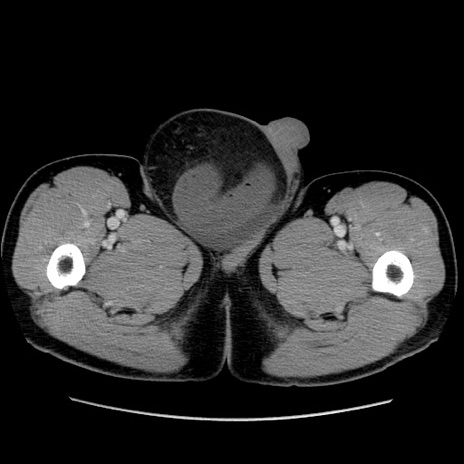

症例34(横断像)

【症例】60歳代 男性

【主訴】右鼠径部膨隆

【現病歴】1年程前より右鼠径部膨隆あり。自己にて還納可能だったため放置していた。3時間前より右鼠径部の脱出を認め、還納困難となり受診。

【身体所見】右鼠径部に小児頭大の膨隆あり。弾性硬であり、用手還納は困難。左鼠径部にも膨隆を認める。脱出はなし。

【データ】WBC 15500、CRP 測定なし